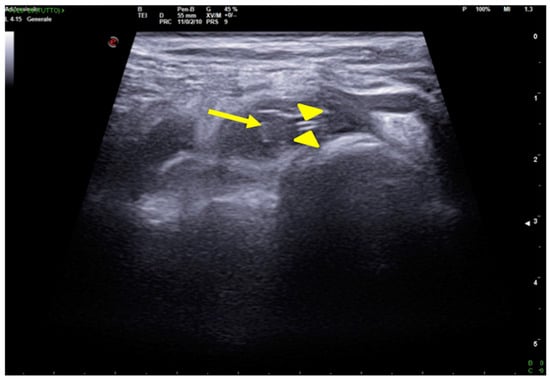

2.1. Atelectasis